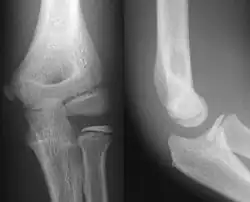

![]() AP and lateral elbow X-ray | |

- Elbow - AP and Lateral. Radial head projections available on request

-

Lateral projection -

Anteroposterior projection -

Left elbow by 30 degrees internal oblique projection -

Left elbow by 30 degrees external oblique projection